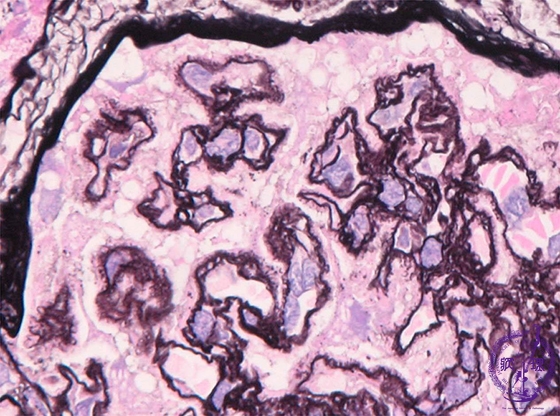

Microscopic findings (PAM? HE,high power view): Basement membrane deposits form spikes which protrude from the subepithelial aspect (red arrows). Additionally, the basement membrane focally demonstrates duplication (blue arrows), categorized as stage II - III.